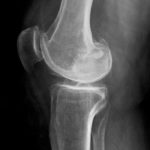

Тазобедренный сустав — сложная анатомическая конструкция костно-суставного соединения, состоящая из полусферической головки бедренной кости и тазовой чаши. Область контакта между двумя сегментами шарнирного сочленения покрыта хрящевым слоем, который распределяет статическую и динамическую нагрузки в суставном блоке, уменьшает трение между анатомическими структурами во время движения.